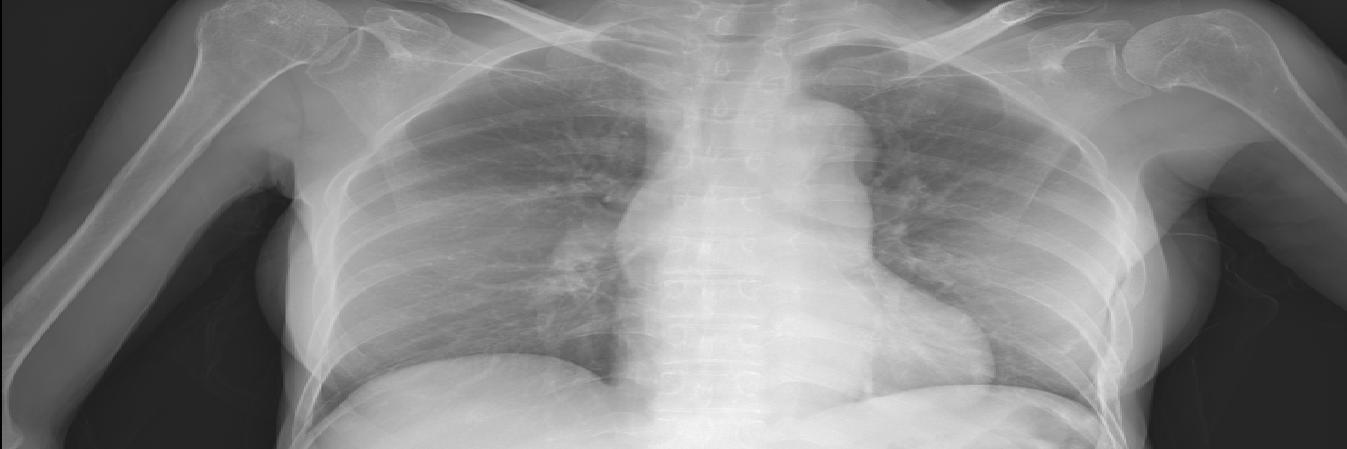

2020๋…„ ์•ˆ์‹ฌํด๋ฆฌ๋‹‰ ์ง„๋ฃŒ๋Š” ์ผ๋ฐ˜ ํ˜ธํก๊ธฐ ๋‚ด๊ณผ์—์„œ ์ง„๋ฃŒ ์ง„ํ–‰ ํ›„ ์ฝ”๋กœ๋‚˜ ํ™•์ง„์ด ์˜์‹ฌ๋  ์‹œ, ๋ณธ๊ด€ ์ถœ์ž…๊ตฌ์— ์žˆ๋Š” ์Œ์••์ง„๋ฃŒ์‹ค์—์„œ ์ง„๋ฃŒ

๋ฐ ํ‰๋ถ€ X-Ray ์ดฌ์˜, ํˆฌ์•ฝ์„ ์ง„ํ–‰ํ•˜์˜€๋‹ค.

๋ฐœ์—ด์ด ์—†์ง€๋งŒ ํ˜ธํก๊ธฐ ์ฆ์ƒ์ด ์žˆ๋Š” ๊ฒฝ์šฐ๋Š” ์™ธ๋ž˜๋กœ ์ง„์ž…, ์Œ์••์‹œ์„ค์ด ์žˆ๋Š” ์•ˆ์‹ฌํด๋ฆฌ๋‹‰ ์ง„๋ฃŒ์‹ค๋กœ ์•ˆ๋‚ดํ•˜์—ฌ ์ง„๋ฃŒ ๋ฐ ํ‰๋ถ€ ๋ฐฉ์‚ฌ์„  ์ดฌ์˜์œผ ๋กœ ํ๋ ด ์—ฌ๋ถ€๋ฅผ ํ™•์ธํ•˜๊ณ  ์ฝ”๋กœ๋‚˜19๊ฐ€ ์˜์‹ฌ๋  ์‹œ ์„ ๋ณ„์ง„๋ฃŒ์†Œ ์žˆ๋Š” ๋Œ€ํ•™๋ณ‘์›์œผ๋กœ ์ด์†กํ•˜์˜€๋‹ค. ์ฝ”๋กœ๋‚˜ ๊ฒ€์‚ฌ๊ฐ€ ํ•„์š”ํ•œ ๊ฒฝ์šฐ์—๋Š” ์‹ ๊ด€ ํ›„ ๋ฌธ ๊ฒ€์‚ฌ์†Œ์—์„œ PCR ๊ฒ€์‚ฌ๋ฅผ ์ง„ํ–‰ํ•œ ํ›„ ๊ท€๊ฐ€ ์กฐ์น˜ํ•˜์˜€๋‹ค.

ยท ํ‰๋ถ€ X-ray ์ด์ƒ ์†Œ๊ฒฌ

์ดฌ์˜

์ด์ƒ ์†Œ๊ฒฌ ๆœ‰ ์ด์ƒ ์†Œ๊ฒฌ ็„ก

์ฝ”๋กœ๋‚˜ PCR๊ฒ€์‚ฌ ์ง„ํ–‰

PCR ์–‘์„ฑ PCR ์Œ์„ฑ